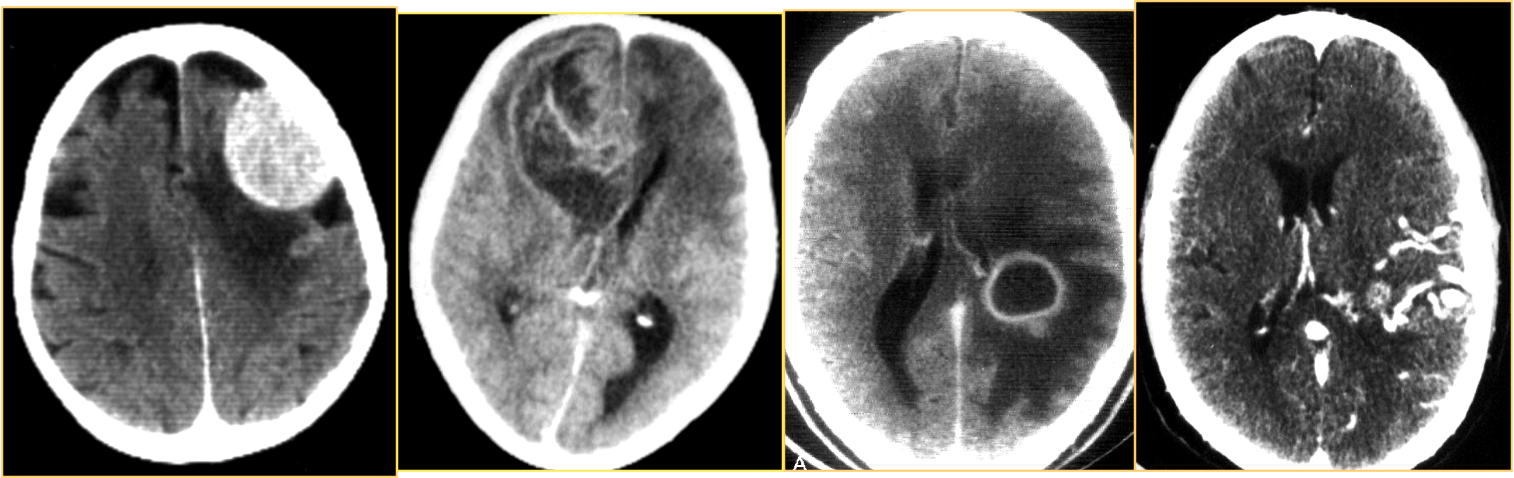

| Hypodense | Hyperdense |

|---|---|

| CSF 0-15HU | Recent CSF 60 -90 HU |

| Brain Edema 20 HU | Calcifications >100HU |

| Cyst (? content) | Some tumors |

| Fat 10-300 HU Air 1000 HU | Protienous fluids |